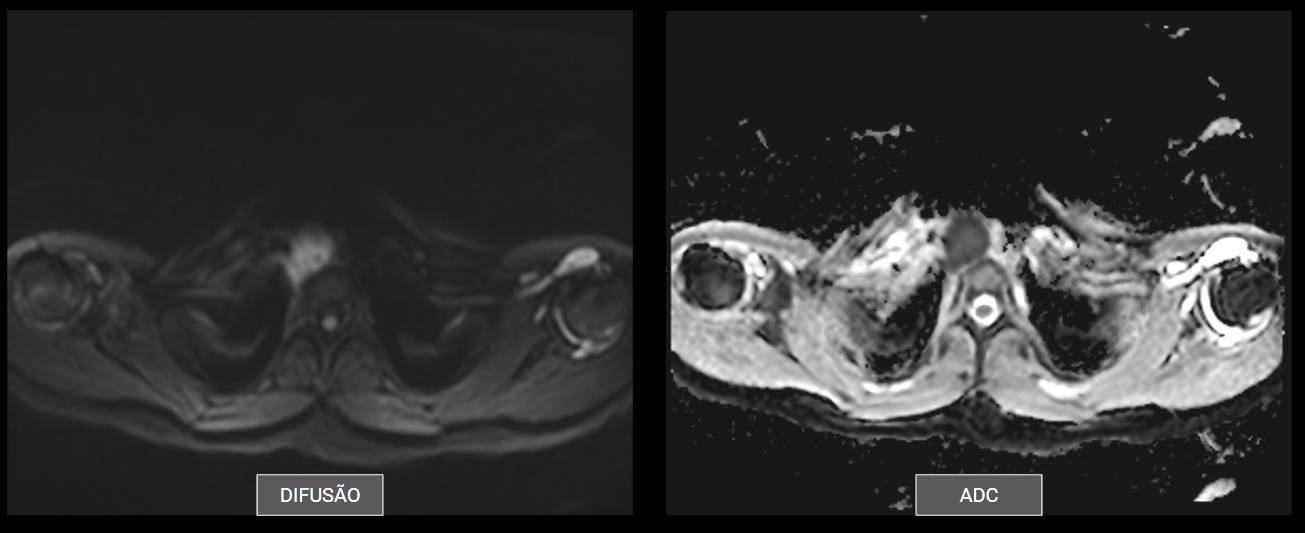

Ressonância do mediastino: